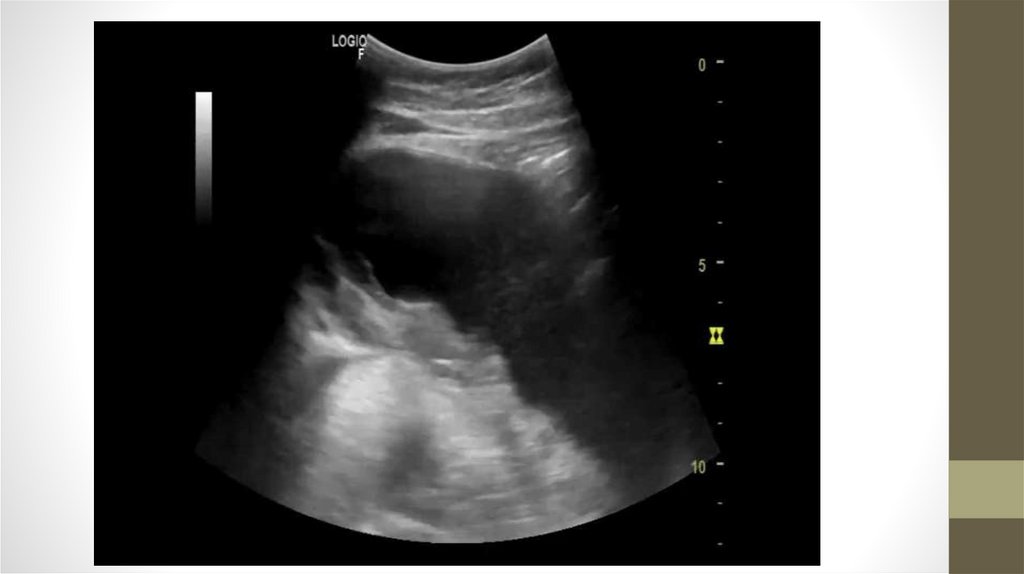

Изменения в поджелудочной железе

Поджелудочная железа - это крупный орган

пищеварительной системы, который принимает

важное участие в переваривании пищи.

Поджелудочная железа наиболее часто

страдает при:

- употреблении алкоголя

- неправильном питании

- отравлениях

- травмах